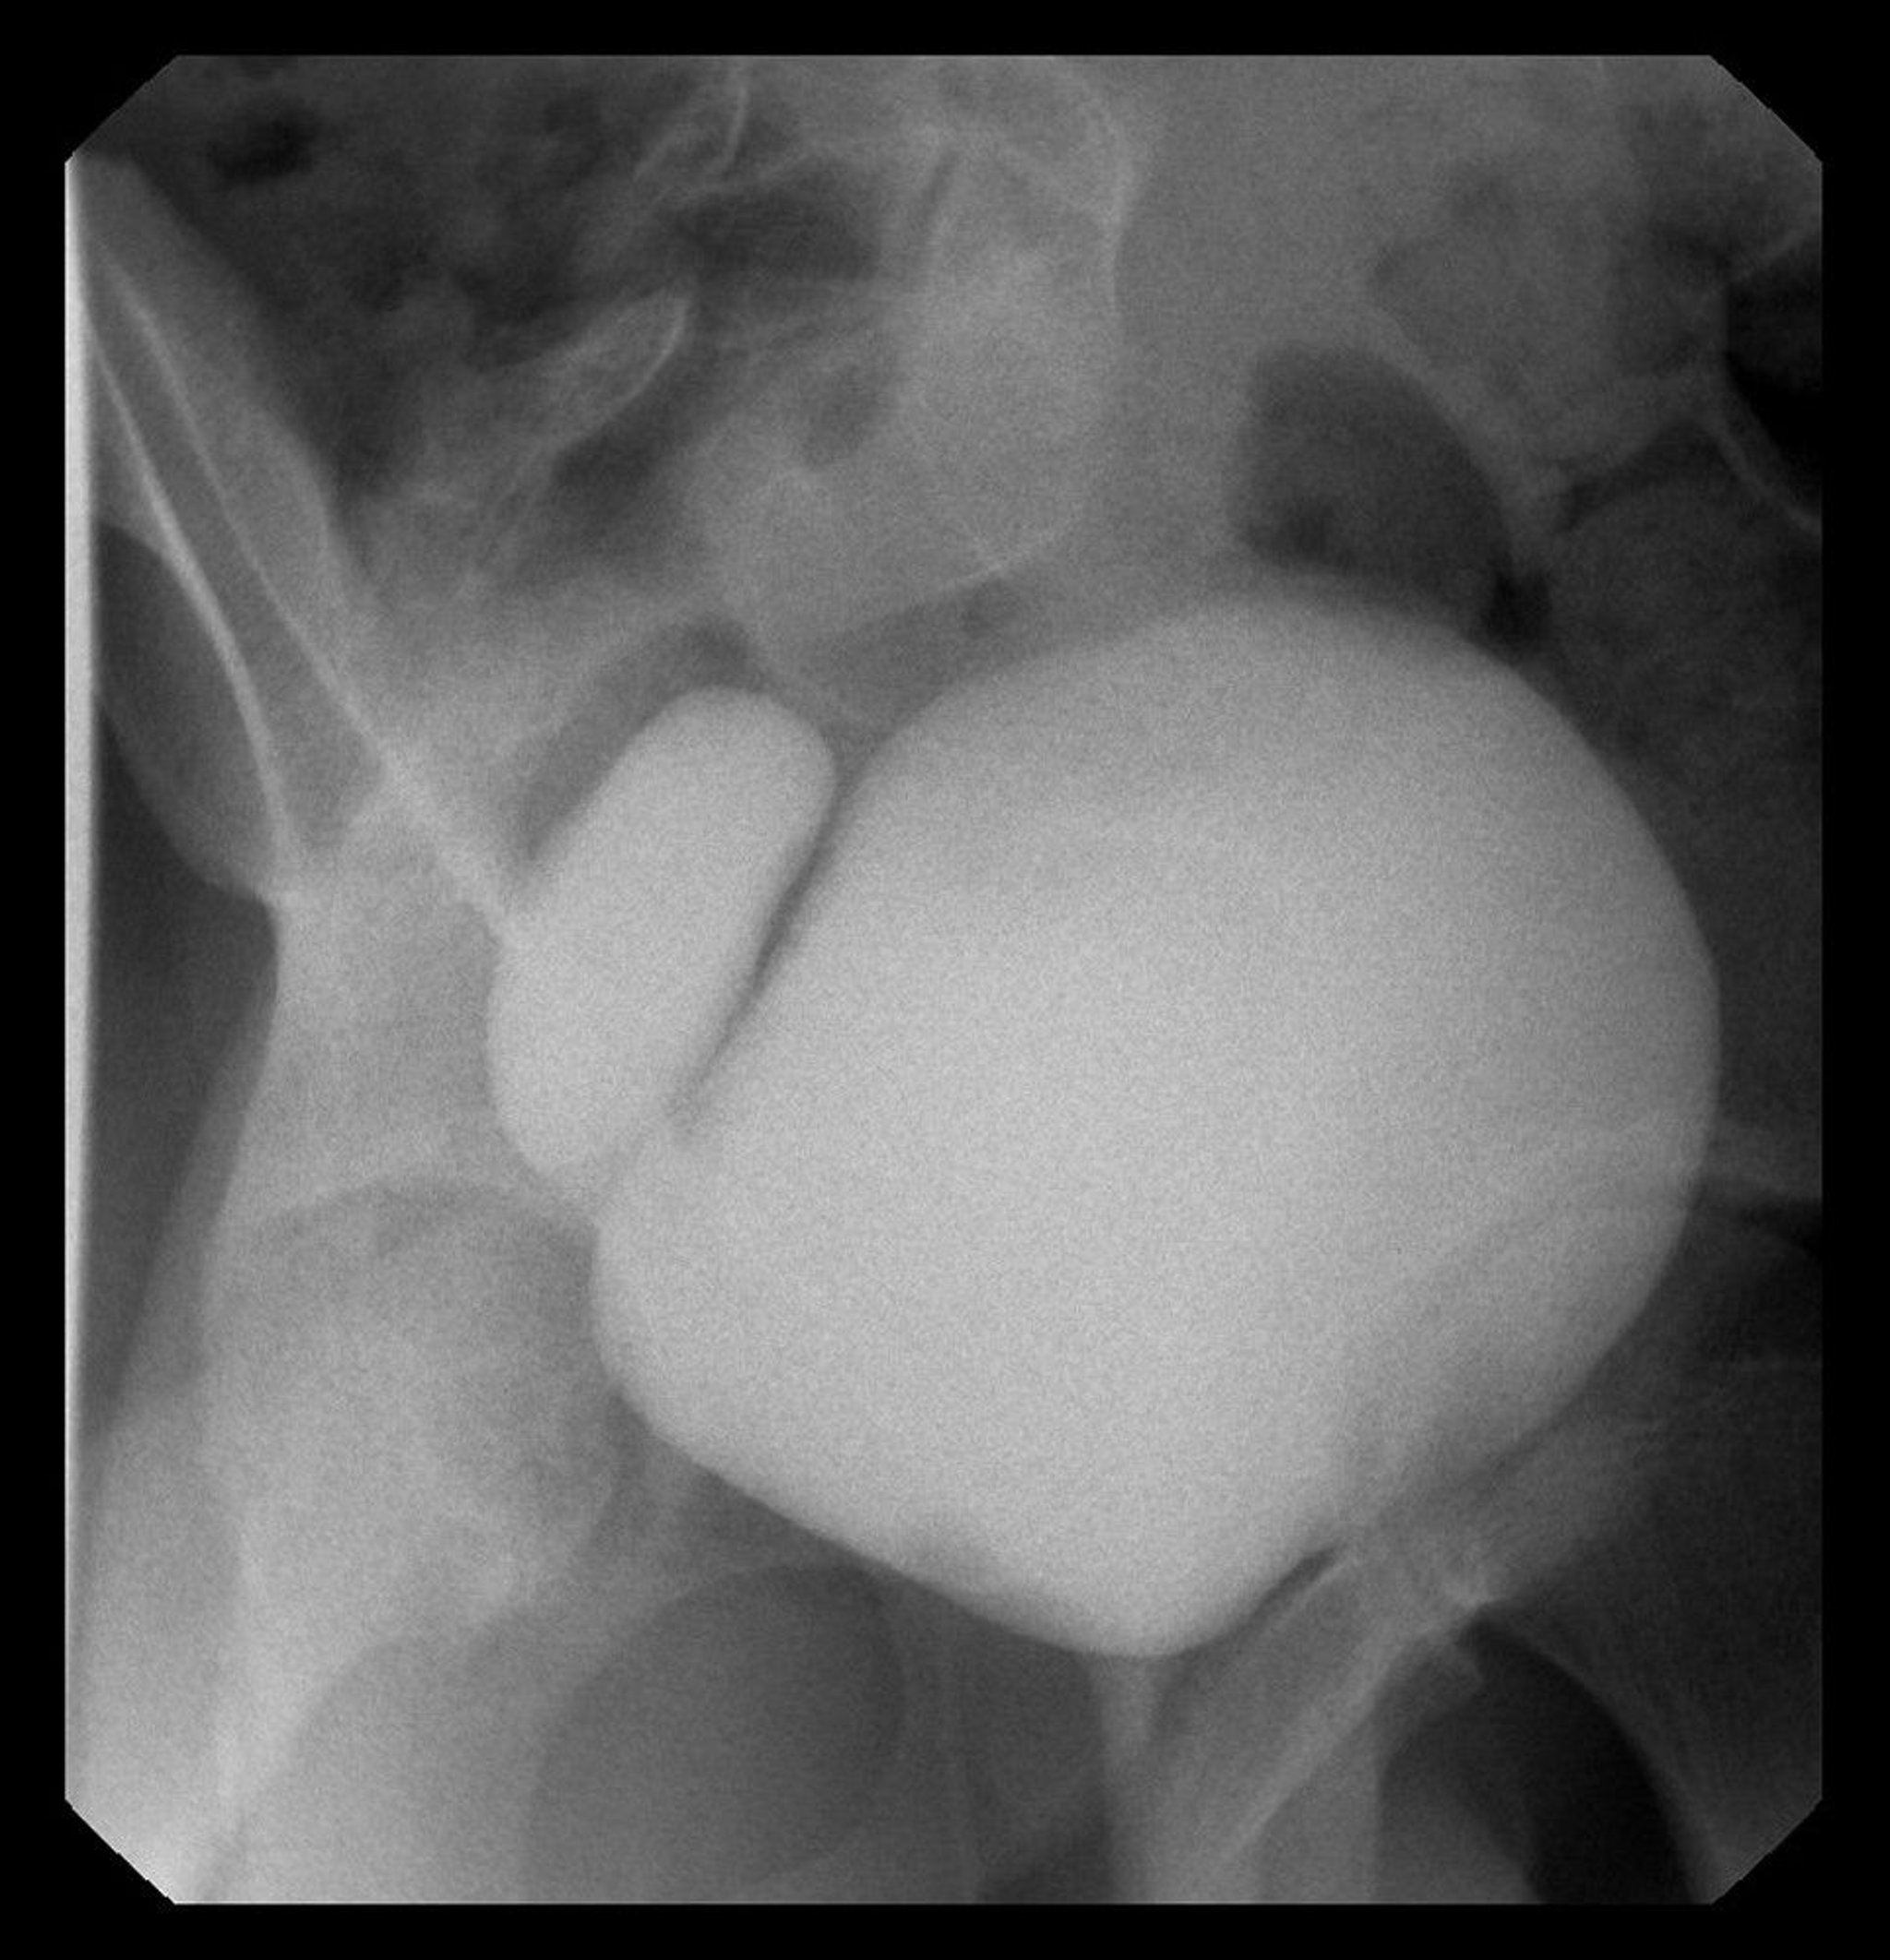

Bladder Diverticulum

This image shows a cystogram with right-sided bladder diverticulum.

Image courtesy of Drs. Ronald Rabinowitz and Jimena Cubillos.